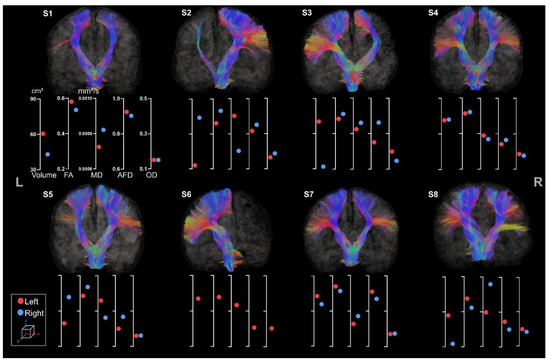

3.2.2. Corpus Callosum

3.3. Atlas-Based Tracts Extraction